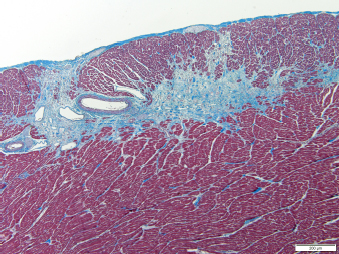

Five weeks after surgery, the otter was found deceased in its enclosure without any clinical signs prior to death. The histologic postmortem lesions included extensive myocardial fibrosis (Fig. 2), multifocal renal interstitial fibrosis, hypertrophy and mineralization of the tunica media of meningeal vessels, and incidental sarcocysts scattered throughout myofibers. The cause of death was presumed to be secondary to significant myocardial fibrosis. No evidence of lymphoma was found in the remaining evaluated tissues, including the heart, kidney, liver, mesentery, brain, thyroid, lymph node, small intestine, eye, pawpad, skeletal muscle, tongue, trachea, lung, esophagus, stomach, pancreas, adrenal glands, urinary bladder, ovaries, and uterus.

Fig. 2. Histopathologic image of the left ventricular wall in a North American river otter showing extensive areas of myofiber loss with replacement by fibrosis. Artery present displays segmental thickening of the tunica media by amorphous hyaline material or fibrosis. Masson’s trichome stain. Scale bar=200 micrometers.